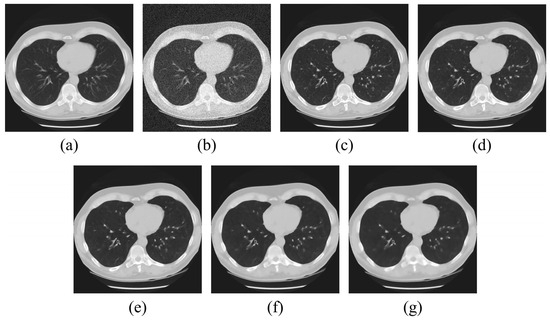

2.2. Median Modified Wiener Filter (MMWF) Modeling

2.3. Region-Growing-Based Segmentation Algorithm Modeling